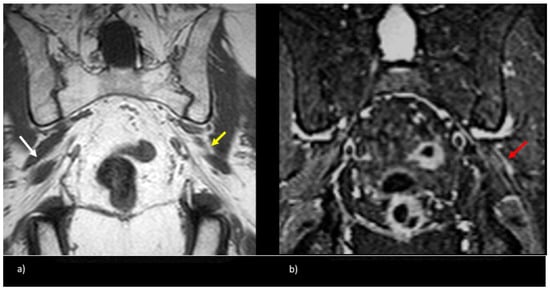

Figure 4.

Patient with a symptomatic type II variant and a split right sciatic nerve. Axial (a) coronal (b) T1-weighted sequence, showing the two components of the split sciatic nerve (white arrow). Axial (c) and coronal (d) T2-weighted IDEAL sequences demonstrate the split sciatic nerve, with the common peroneal (white arrow) and the tibial (yellow arrow) nerve components seen distinctively. There is also increased nerve caliber and increased nerve T2 signal involving the split right sciatic nerve, relative to the normal caliber and T2 signal of the left sciatic nerve (red arrow).